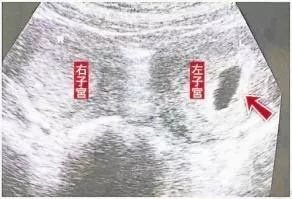

驻马店市平舆县的李女士今年48岁,平日里身体健康,近日,突然出现腹部疼痛等症状。在家人的陪同下,遂到当地医院就诊。医院医务人员接诊后,立即为李女士行盆腔彩超,结果提示为,子宫发育异常,偏右侧子宫颈纳囊,偏左侧子宫低回声团(肌瘤),偏右侧子宫颈增厚。

没错,李女士的子宫竟然有两个宫颈、两个宫腔,也就是我们所说的双子宫!

经过系统检查,李女士除了双子宫,还存在左侧子宫肌瘤,右附件区囊肿及盆腔子宫内膜异位症,这些疾病严重地影响到李女士的身心健康。

紧张的术前准备后,贺全勤主刀,李贺月、符小春为助手的妇科手术团队,在医院麻醉科手术室医务人员的密切配合下,如期进行。腹腔镜下发现,患者双子宫分布于盆腔两侧,左侧子宫增大如孕2月余,左后壁可见一大小约6.0x5.0c肌瘤样结节,右侧子宫稍增大,可见小肌瘤样结节。贺全勤为李女士实施了全麻腹腔镜下双子宫+双侧输卵管切除+盆腔粘连松解术,术程顺利,患者平安,李女士于术后第6天康复出院。